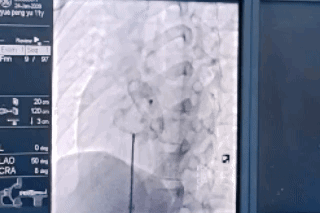

近日, 我院心脏大血管外科在 上海儿童医学中心刘廷亮主任的支持指导下, 为一名25mm大型房间隔缺损患儿, 成功实施经皮房间隔缺损封堵术。 术后第二天, 患儿即可自如下床活动。 该术式以毫米级切口、免开胸的微创优势, 彰显了我院在 先天性心脏病微创治疗领域的 硬核技术实力。

房间隔缺损作为儿童先心病的常见类型,传统手术需开胸、建立体外循环,创伤较大,住院周期长(需1-2周),遗留疤痕对患儿的生理与心理均造成较大影响。 释放封堵装置,推拉稳固锚定点 而封堵治疗仅在腿部以2-4mm的穿刺伤口便可实施心内缺损的封堵,不损伤心内结构,术后2-3天即可出院,做到无痕愈合,是目前治疗继发孔型房间隔缺损首选的微创治疗方案。